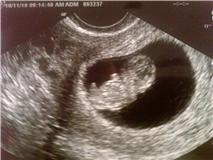

Well, here is what we have been hiding the last ten weeks:). A little

Gummie Bear!!! We have been waiting to make the big announcement because we wanted to make sure everything was okay. Yesterday we had a doctor's appointment and they said everything was looking really good and healthy, so we decided it was time to share our happy news.

We are

soooooo excited! Baby F really put on a show for Mom and Dad yesterday during the appointment. It was waving, kicking it's little stub legs together, and even doing a little dance. Such a show off already:).